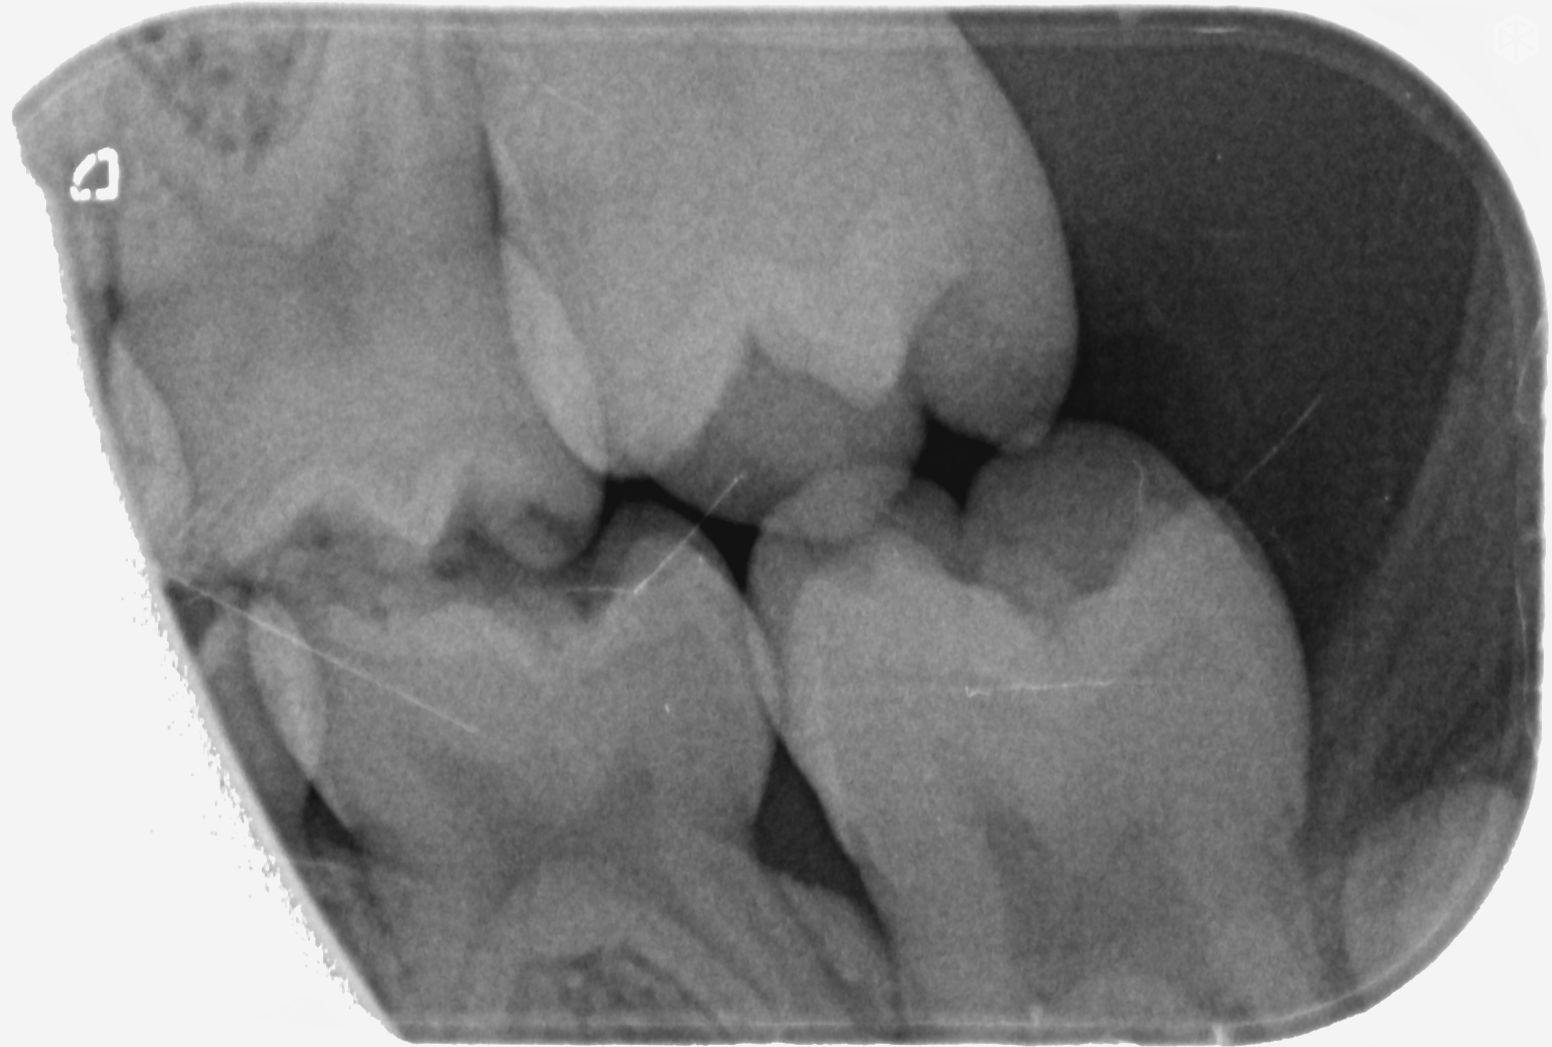

Beste tandarts, Bijgevoegd 2 XR-beelden van de melktand kiezen van onze dochter van 6. Bij een controle bij onze tandarts werden haar tanden visueel gaaf bevonden, maar wou men toch graag een foto maken. Hierop ziet de tandarts 6 gaatjes die ze in 3 sessies wil open maken en vullen. Uiteraard willen wij dat de gaatjes behandeld worden indien nodig. Echter doordat we het gevoel hebben dat er bij elk van ons steeds meerdere problemen gevonden worden waar we geen hinder van ondervinden, zou ik graag een tweede opinie vragen. Omdat ik zelf de beelden niet kan interpreteren, mijn vraag dus of er effectief 6 gaatjes te zien zijn en of het vullen hiervan aanbevolen is. Alvast bedankt voor uw hulp!

Ik zie mogelijk een gaatje in de 55 en 54. Mogelijk omdat er een overprojectie is. Maar dusdanig klein dat ik zou afwachten tot uw dochter wat ouder is. Na een jaar een vergelijking foto. Maar ik zie geen zes op deze foto's.